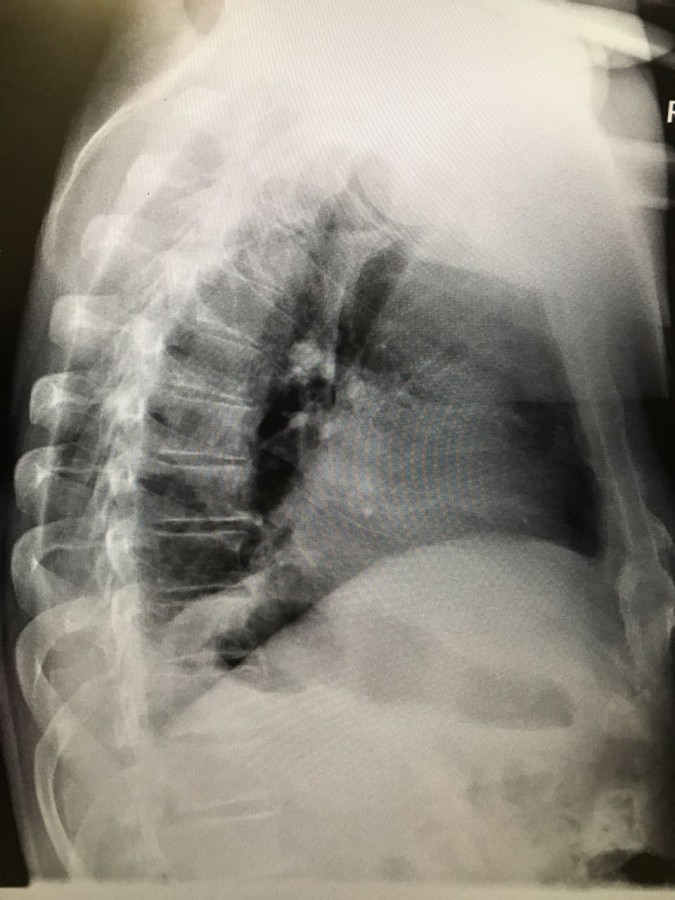

На рентгене гиповентиляция - признак центрального рака

Обсуждалось в Госпитале Ослабленных Сердец